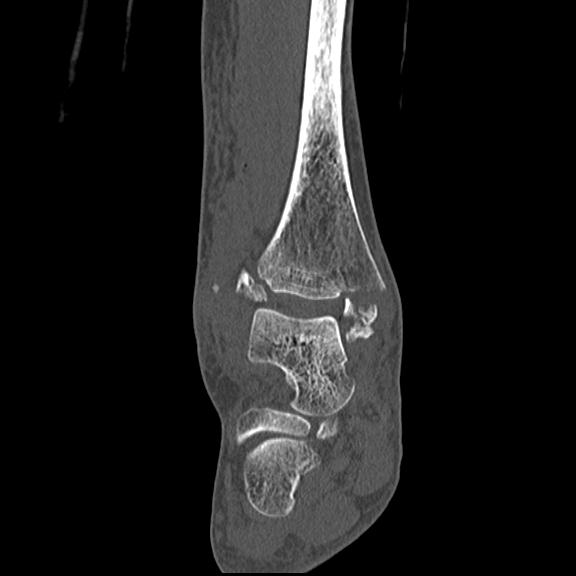

102755 1/4 2R 1/15 2R 右足関節 68歳女性 右三果脱臼骨折